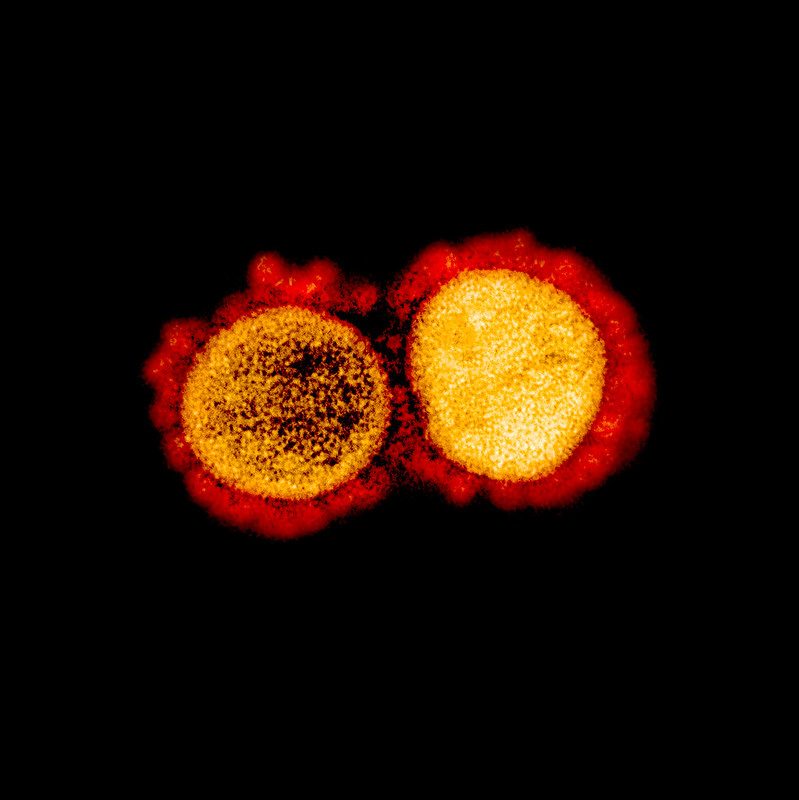

Resulta que los investigadores de este centro sacaron fotografías microscópicas del coronavirus atacando células humanas, mostrando detalles nunca antes vistos.

Las distintas imágenes del COVID-19 se obtuvieron con un microscopio de electrones y después fueron coloreadas artificialmente para mostrar diferentes detalles del patógeno.

Este microorganismo que tiene al mundo en cuarentena es solo una cadena de ARN, un hilo de proteínas formando un ovillo y que está recubierto de una capa de lípidos con espinas de proteínas que recuerdan a una corona, de ahí el nombre que adopta.

Cómo funciona atacando al ser humano según NIAID «el patógeno usa esas espinas para adherirse a las proteínas de la membrana celular. Cuando lo logra, usa la maquinaria interna de la célula para crear copias de si mismo hasta que la célula infectada implosiona y se rompe, liberando más virus para que infecten las células cercanas. El proceso destroza las células del tejido pulmonar, causando la flema, la inflamación, la fiebre y todos los problemas respiratorios asociados a la enfermedad».

El coronavirus mide entre 120-160 nanómetros de diámetro. Esto significa que son demasiado pequeños para ser vistos con un microscopio óptico y solo observables con un microscopio electrónico.